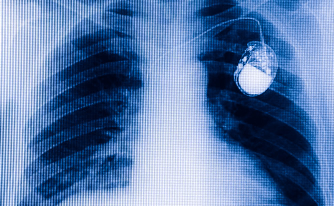

Da circa due mesi mi hanno impiantato un pacemaker: corro qualche rischio durante l’attività subacquea?

Esistono dei pace-maker che sono compatibili con l’immersione (generalmente fino ai 40 m) e altri invece che non lo sono. Dovresti chiedere al tuo cardiologo se il tuo sia tra i primi e, in tal caso, fino a quale profondità. Il tuo ritorno all’attività subacquea dipende anche dalla cardiopatia che ha determinato la necessità di utilizzare tale dispositivo, così come da potenziali condizioni mediche limitanti e terapia farmacologica che potresti assumere. Pertanto, una volta ottenuta, da parte del tuo cardiologo, la conferma che il tuo pacemaker sia compatibile con l’attività subacquea, dovrai recarti presso uno specialista in medicina subacquea per stabilire la tua idoneità alle immersioni e per valutare insieme le eventuali limitazioni cliniche che impedirebbero di immergersi in sicurezza.

La presenza di un pacemaker non rappresenta di per sé una controindicazione assoluta all’attività subacquea. Tuttavia, la possibilità di continuare a immergersi dipende dalle condizioni cardiologiche generali e dalla stabilità del ritmo nel tempo. Per quanto riguarda il dispositivo, non esistono pacemaker “specifici” per la subacquea. I diversi modelli disponibili si differenziano anche per la resistenza alla pressione: in generale, la maggior parte dei pacemaker è testata per resistere a pressioni corrispondenti a immersioni tra circa 20 e 30 metri, mentre alcuni modelli possono avere limiti superiori (fino a circa 40 metri). È importante sottolineare che questi limiti variano in base al dispositivo specifico, per cui è fondamentale fare riferimento alle indicazioni del produttore del modello impiantato. Per questo motivo, è consigliabile informare il cardiologo che eseguirà l’impianto della sua attività subacquea, così da poter scegliere il dispositivo più appropriato e programmare adeguatamente i controlli successivi. In ogni caso, prima di riprendere le immersioni, sarà necessario un periodo di stabilizzazione dopo l’impianto e una valutazione specialistica che confermi l’idoneità all’attività subacquea. Raccomandiamo sempre la massima prudenza e controlli regolari nel tempo.